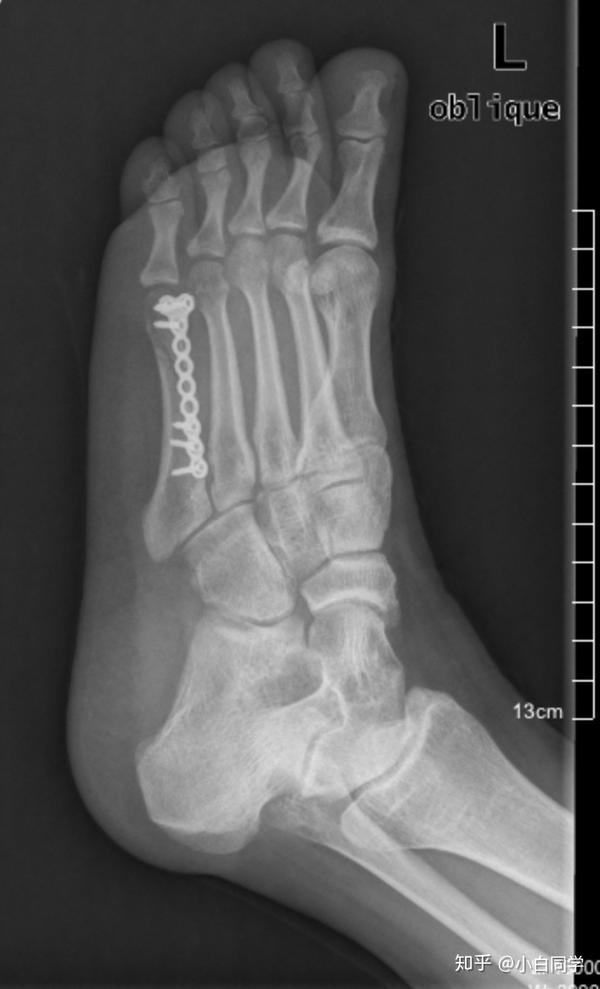

第4足趾末節骨中節骨癒合骨骨折に対してvariable pitch headless compression screwを用いて手術した1例を報告する.患者は42歳の女性で,歩行中,誤って柱に右第4足趾をぶつけて受傷し,同日初診した.初診時単純X線像では第4足趾の末節骨と中節骨の癒合骨に横走する骨折線を認めた.当初,保存的に治療したが,骨折部の転位が徐々に増大して疼痛も持続したため,

第1趾にある種子骨は体重を受ける働きや第1趾の骨を持ち上げる働きもあります。 原因 種子骨を骨折したり、周囲の腱で炎症が起きた状態を種子骨障害と呼びます。 バレエダンサーやランナー、野球のキャッチャーなどでよく見られます。右第23趾基節骨骨折 当院での症例 第23趾基節骨骨折 高岡市在中 74歳 男性 18年9月28日負傷 問診 自宅で暗闇の中でテーブルのあしにつまづき転倒した際に負傷 検査・テスト 第23趾基節骨の限局性圧痛と腫脹、皮下溢血、運動制限、 受傷POINT 指骨骨折とは 指の骨の骨折のことです。 手や指に物がぶつかったり、外から強い力が加わることによって起こります。 男性や高齢者に多く、骨折が起こると痛みや腫れ、熱感(熱をもった感じ)が現れます。 骨折の程度を調べるために、レントゲン検査やCT検査が行われ、治療は保存的治療(安静・固定・鎮痛剤など)もしくは、手術(プレートやワイヤーに